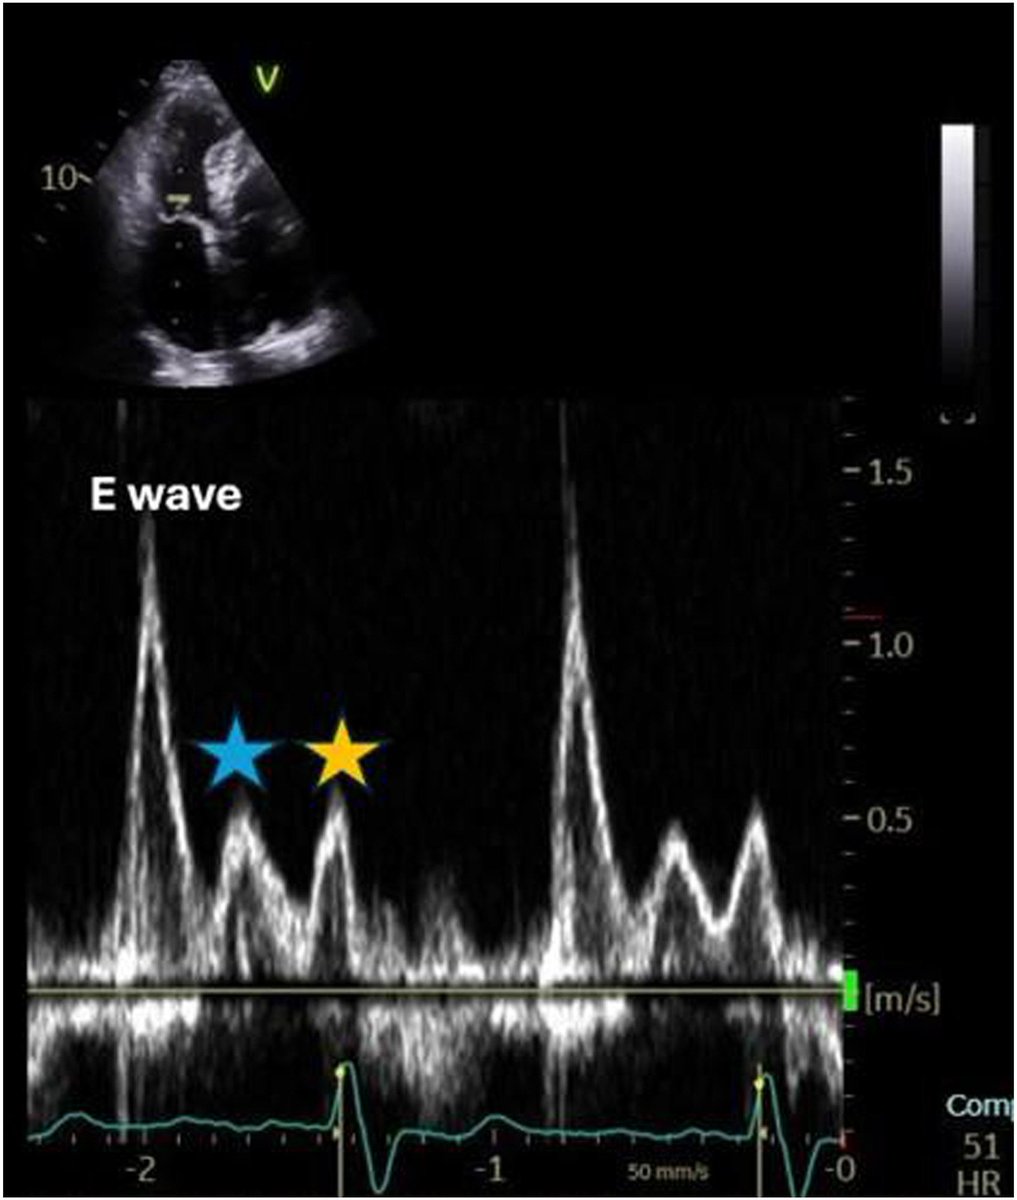

Echo DD guidelines are consensus based and require testing to determine clinical utility. In this multicenter study with gold standard dx, we show poor sensitivity and accuracy for resting and exercise echo criteria. @JACCJournals